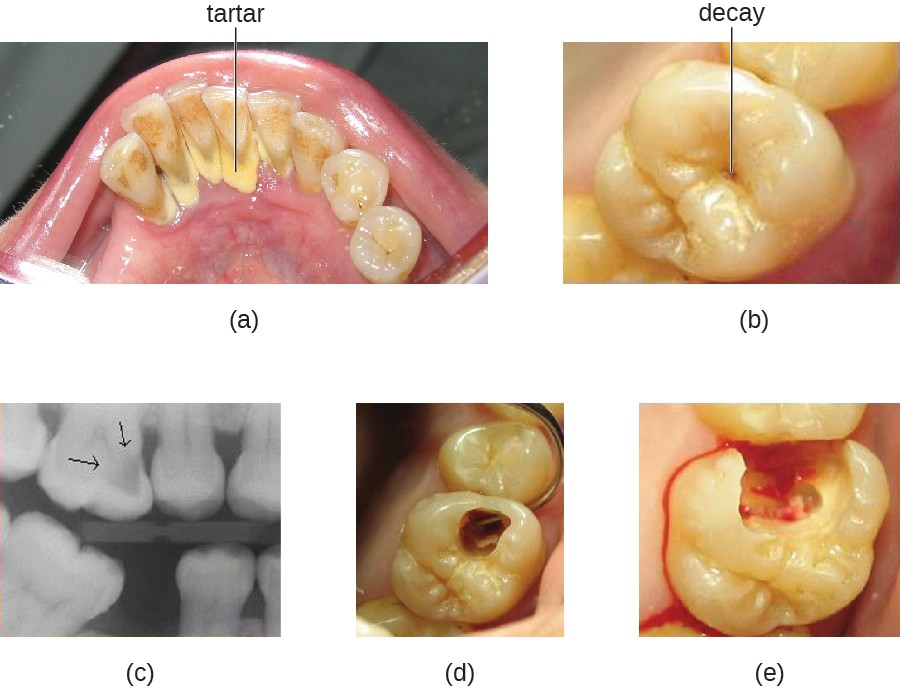

(a) Tartar (dental calculus) is visible at the bases of these teeth. The darker deposits higher on the crowns are staining. (b) This tooth shows only a small amount of visible decay. (c) An X-ray of the same tooth shows that there is a dark area representing more decay inside the tooth. (d) Removal of a portion of the crown reveals the area of damage. (e) All of the cavity must be removed before filling.

Figure 19.8 (a) Tartar (dental calculus) is visible at the bases of these teeth. The darker deposits higher on the crowns are staining. (b) This tooth shows only a small amount of visible decay. (c) An X-ray of the same tooth shows that there is a dark area representing more decay inside the tooth. (d) Removal of a portion of the crown reveals the area of damage. (e) All of the cavity must be removed before filling. (credit: modification of work by “DRosenbach”/Wikimedia Commons)

Some tooth decay is visible from the outside, but it is not always possible to see all decay or the extent of the decay. X-ray imaging is used to produce radiographs that can be studied to look for deeper decay and damage to the root or bone (Figure 19.8). If not detected, the decay can reach the pulp or even spread to the bloodstream. Painful abscesses can develop.